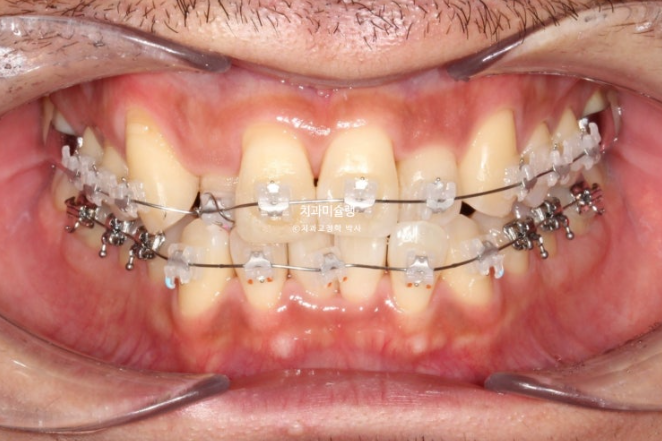

치료를 이어가다가 아래턱 비대칭에 의한 중심선 어긋남을 하기 위해 아래쪽에 교정용 나사도 하나 심었습니다.

25.09

그리고 드디어 치료가 마무리 되었습니다.

25.10

거의 맞아진 중심선

교합은 물샐틈 없는 1급 교합관계를 보입니다.